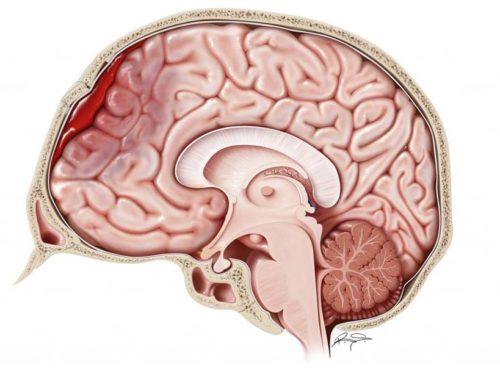

При черепно-мозговых травмах формирование гематомы может происходить не только в области удара, но и на противоположной стороне. Гематомы классифицируют в зависимости от их локализации:

- Эпидуральные – формируются между костями черепа и твердой мозговой оболочкой. Распространению кровоизлияния препятствуют костные швы (венечный, сагиттальный, ламбдовидный), к которым прикреплена оболочка мозга. По этой причине гематома не может перейти из одной области в другую. Двояковыпуклая форм.

- Субдуральные – процесс происходит между паутинной и твердой оболочками мозга. Гематома не ограничена в распространении, может находиться над 2-3 долями полушарий. Серповидная форма.

- Внутримозговые – скопление крови в тканях мозга (пропитывание участка). Круглая форма.

- Внутрижелудочковые – появляются при травмах сосудов в желудочках мозга, затекании крови из поврежденных участков.

Кровоизлияние может быть комбинированным, то есть сразу появляться в разных участках головного мозга. Например, средняя левосторонняя эпидуральная и малая правосторонняя субдуральная гематома. Важно!Эпидуральные гематомы не могут образоваться на основании мозга вследствие того, что кости черепа плотно сращены с твердой оболочкой мозга.